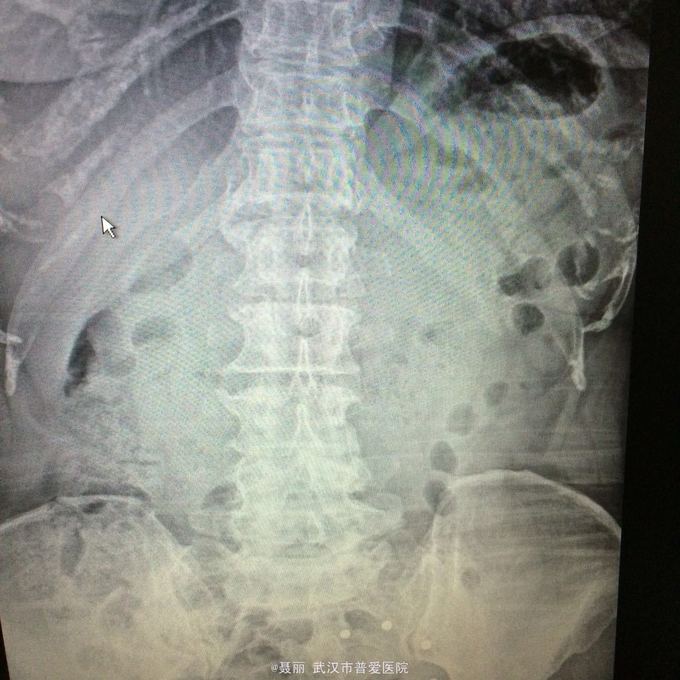

患者,女,51岁。 反复腰痛并间歇性跛行5年余,加重并左侧臀部2月余。 患者于5年前无明显诱因外伤诱因出现腰痛,不伴有双下肢麻木、乏力及间歇性跛行,卧床休息后好转,间歇发作,进行性加重。 既往史:有高血压病、糖尿病病史,否认有药物过敏

:L4/5棘突间轻压痛,叩痛,棘间左侧椎旁压痛;双下肢肌力、肌张力正常,病理反射未引出。 门诊资料:外院行腰椎CT检查示:L3-S1椎间盘膨出,L4椎弓崩裂并向前滑脱(重度)椎管狭窄。 入

入院诊断:、腰椎滑脱(L4/5 峡部裂性) 诊疗计划:1:完善有关检查2卧床休息,行改善微循环、3.腰椎后路复位减压植骨融合术

行改善微循环、3.腰椎后路复位减压植骨融合术 腰椎滑脱(L4/5 Ⅱ度)、腰椎管狭窄症(L3/4)、腰椎间盘突出症(L5/S1)查体双下肢感觉、活动无明显异常。双下肢末梢血液循环可。换药见伤口对合良好,无明显红肿渗出。伤口已拆线。嘱加强双下肢活动及功能锻炼,避免下肢深静脉血栓,主动及被动四肢活动,预防血静脉及床褥形成,加强腰背肌锻炼,适量康复功能锻炼。一个月后来复查伤口愈合好,疼痛没有,活动可